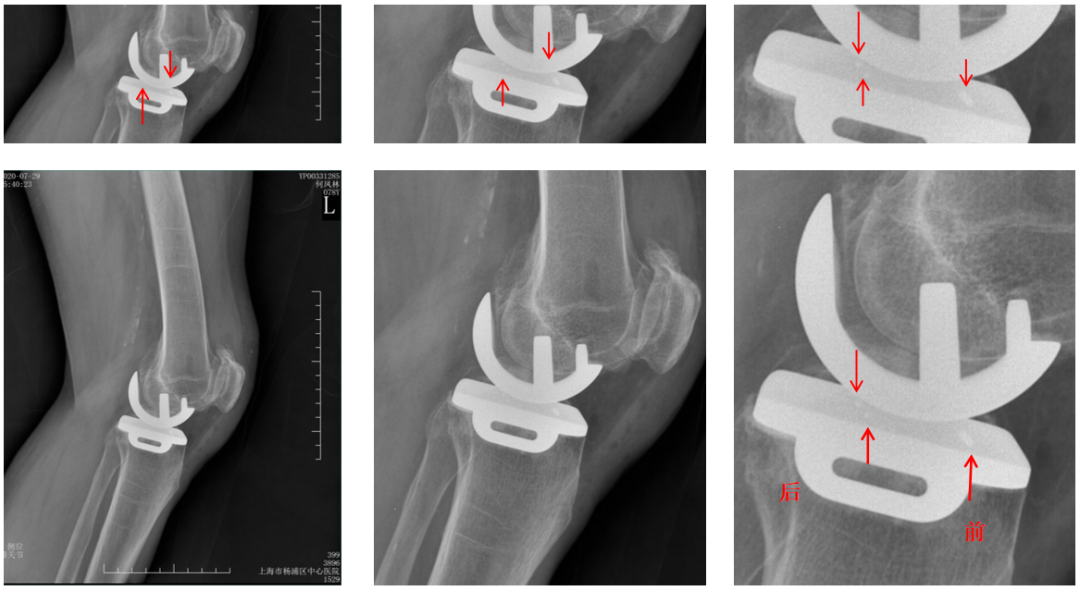

辨认bearing内的标识(X-ray侧位)

bearing 内的标识:点和线段“ .—. ”线段显示为“—”在前,点显示为“.”在后

辨认bearing内的标识(透视片侧位)

bearing 内的标识:点和线段“ .—. ” 线段显示为“—”在前;点显示为“.”在后

三、垫片(bearing)脱位

Bearing脱位多发生在UKA术后早期,发生率0.6%左右。

Bearing脱位主要原因包括:屈伸间隙不平衡,MCL损伤,以及假体位置不良,罕见bearing破裂。

Bearing脱位在正位片上显示股骨与胫骨假体关节面接触,侧位片显示bearing位于关节囊前方或者后方。